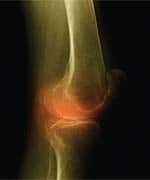

Doctors, Therapists Tout Pain-Relief BenefitsJay Nielsen, MD, injured his knee so severely while hiking that he was left unable to stand. As medical director of the Wellness Rx clinic in Maumee, OH, which treats patients suffering from arthritis, fibromyalgia, and similar disorders, Dr. Nielsen was well versed in pain-management strategies before his injury. After hurting his knee, he underwent x-rays, physical therapy, chiropractic care, and various other treatments. After nearly three months, however, he realized that he had damaged the cartilage in his knee and would require surgery.

Prior to undergoing surgery, Dr. Nielson tried Natural Relief 1222 one morning and noticed a significant improvement in his knee pain after just 20 minutes. He continued to apply the cream throughout the day, and by evening, his knee pain had diminished dramatically. After using the cream for three weeks, his knee had improved so much that he was able to get around almost normally. Dr. Nielsen cancelled his surgery and continued to use Natural Relief 1222, applying the cream four times a day. “I’m now down to one application a day,” he told Life Extension. “I’ll still have to have my knee ‘scoped’ for the cartilage, but I find it amazing that this product can postpone surgery for a knee that had me confined to a chair and unable to walk.” Dr. Nielsen calls Natural Relief 1222 the most important product he has seen for treating joint pain since glucosamine. His experience led him to recommend the cream to his patients, who have observed similar results using it. Nielsen estimates that he has at least 600 patients who use Natural Relief 1222 regularly. Dr. Nielsen works with Lee Kramer, who owns the Wellness Rx clinic and is a licensed massage therapist specializing in myofascial pain management. (Myofascial pain management seeks to counter restriction of the fascia, the seamless web of connective tissue covering and connecting the muscles, organs, and skeleton in the body. Injuries, stress, trauma, and poor posture can cause restriction of the fascia.) Kramer and his staff tested Natural Relief 1222 extensively before recommending it to their patients. “The pain relief was immediate, and we’re not an easy sell,” Kramer told Life Extension. “We’ve tried every other ointment and cream on the market, including all the products with capsaicin or counter-irritants, and this is something different. Rather than heating or cooling the skin to mask pain, Natural Relief 1222 actually seems to stop the pain, apparently because it has an anti-inflammatory effect.” According to Kramer, Natural Relief 1222 is one of the clinic’s most popular products. Its sales have outpaced those of other topical creams since the clinic began offering it two years ago. Kramer’s own experience with Natural Relief 1222 left him with no doubt about why his patients are devoted to the product. After injuring his knee, Kramer applied Natural Relief 1222 to the injury site. Within an hour, his pain was gone, and he did not require another application for three days. First Defense Against Chronic PainDavid William Johnson, MD, of Evansville, IN, reports that Natural Relief 1222 is popular with his chronic pain patients, especially those suffering from fibromyalgia. An estimated 3.7 million people in the US—primarily women who are diagnosed with the disease in their thirties and forties—have fibromyalgia.1 A painful rheumatic condition, fibromyalgia is characterized by diffuse or localized pain, tenderness, and stiffness of the skeletal muscles and connective tissues. Fibromyalgia is also frequently accompanied by sleep disturbances and chronic fatigue. In addition to suffering persistent, widespread musculoskeletal pain, people with fibromyalgia often must cope with friends, family, and health care professionals who dismiss the disease as a psychosomatic disorder. Despite the widespread prevalence of fibromyalgia, its cause remains unknown. According to Dr. Johnson, Natural Relief 1222 provides results that are superior to those of other topical creams his patients have tried. Many apply the cream at night and find that it helps them sleep better, which in turn helps to mitigate the chronic fatigue associated with fibromyalgia. Dr. Johnson suspects that Natural Relief 1222 may be especially effective for fibromyalgia patients because it addresses muscle pain, whereas many other products are designed to primarily address joint pain. “I have pharmaceutical reps coming in all the time to tell me the great things about their products, but I rely more on what my patients tell me,” Dr. Johnson explains. “Natural Relief 1222 isn’t a cure, but it gives my patients relief so that they can sleep restfully and function better.”

One in three adults in the US—approximately 66 million people—suffer from arthritis or symptoms of chronic joint pain, according to the Arthritis Foundation.2 One of the most prevalent chronic health problems, arthritis is the leading cause of disability among Americans over the age of 15. Second only to heart disease as a cause of work disability, arthritis limits simple everyday activities such as walking, dressing, and bathing for more than 7 million Americans. Arthritis is responsible for an estimated 39 million physician visits and more than a half million hospitalizations each year.2 Like fibromyalgia, arthritis is usually a chronic condition, characterized by pain, stiffness, inflammation, swelling, and even destruction of the joints. The severe, chronic pain that often accompanies conditions like fibromyalgia and arthritis can greatly compromise a person’s quality of life. Moreover, chronic pain can lead to depression, increased stress, and reduced activity levels, which can further exacerbate symptoms, producing a vicious cycle of worsening pain, depression, and inactivity. While many people suffering from arthritis and fibromyalgia seek relief from over-the-counter medications and prescription nonsteroidal anti-inflammatory drugs (NSAIDs), others avoid these drugs for fear of the adverse side effects associated with many of them. It was precisely this predicament that led H. Edward Troy, PhD, to devote 14 years of his life to developing an all-natural, topical cream that could provide fast, safe, effective relief from joint and muscle pains. | ||||